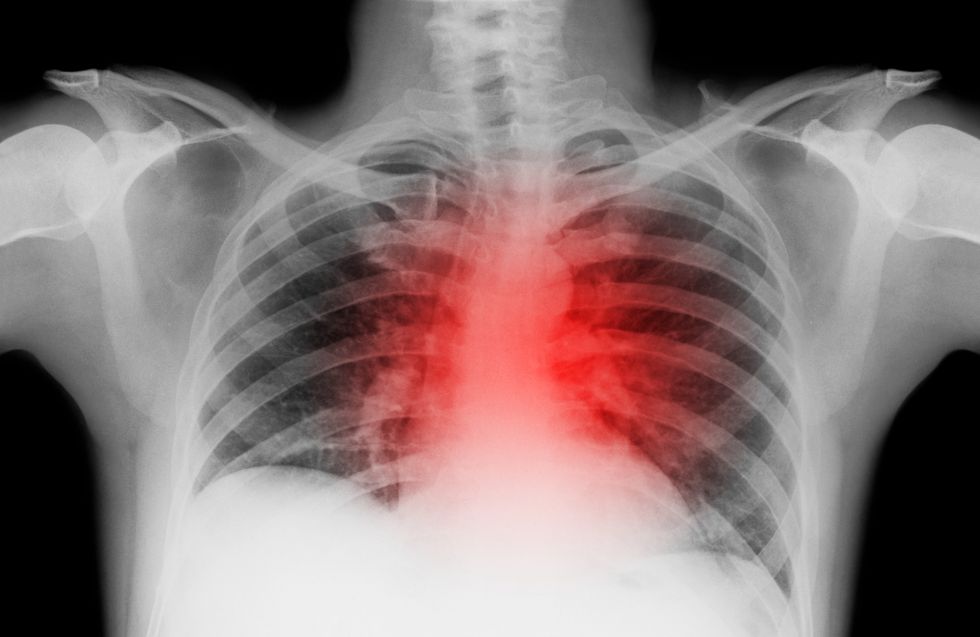

Deaths from heart attacks have plummeted by nearly 90 per cent over the past five decades - yet medical experts are warning of a surge in three other deadly cardiovascular conditions.

The findings showed that heart attacks, which accounted for 54 per cent of all heart disease deaths in 1970, now represent just 29 per cent of cardiovascular fatalities.

Meanwhile, deaths from the three emerging conditions - heart failure, arrhythmias and hypertensive heart disease - have risen from nine per cent of heart disease deaths in 1970 to 47 per cent in 2022.